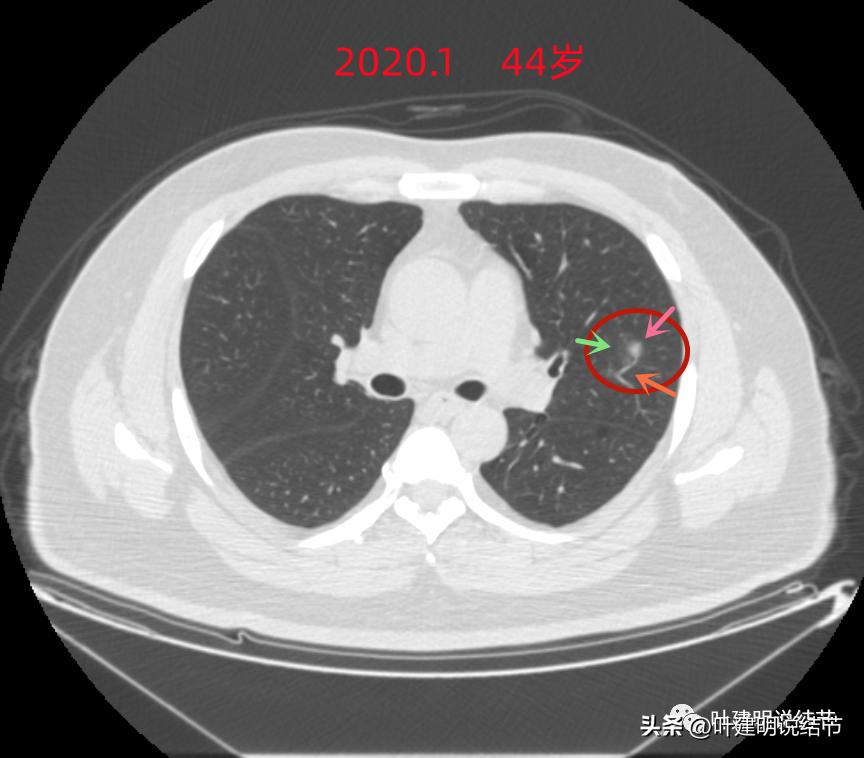

前几天有位同事联系我,说她在省外的有位朋友查出来有肺结节,得知我入职浙江大学医学院附属杭州市肿瘤医院了,一定要叫她帮忙联系,让我看看其胸部CT片,或者约个时间来杭州看。但我告诉同事,现在微信这么方便、影像资料的传输如此便捷,根本不必亲自来杭州,建议将影像资料发给同事,再转发给我看就可以了,如果没有电子版的图像资料,可以到检查的医院去拷贝的,打包发我邮箱就可以,以免舟车劳顿之苦。次日,我拿到了其影像资料。一般我是先看最近的CT,对病灶的良性或恶性有初步的判断,再找最早的对比,看有没有变化,得出最终的判断结果。但这位结友因为发现已经2年多了,所以我是先看2020年1月的。我们先来看其当时的片子:

左上病灶1:磨玻璃结节,轮廓清楚伴微血管进入,中间似乎有空泡征,感觉像原位癌或不典型增生;

左上病灶2:混合磨玻璃结节,密度偏高,边缘稍糊,但轮廓相对清,有微血管分支进入,考虑微浸润性腺癌或浸润性腺癌可能大;

左上病灶3:混合磨玻璃结节偏实性,内部密度不均,整体轮廓清,有浅分叶,也有小血管关系密切,考虑浸润性腺癌可能性大;

左上病灶4:舌段磨玻璃结节,边缘显力糊,整体轮廓较清,不典型增生可能性大点。